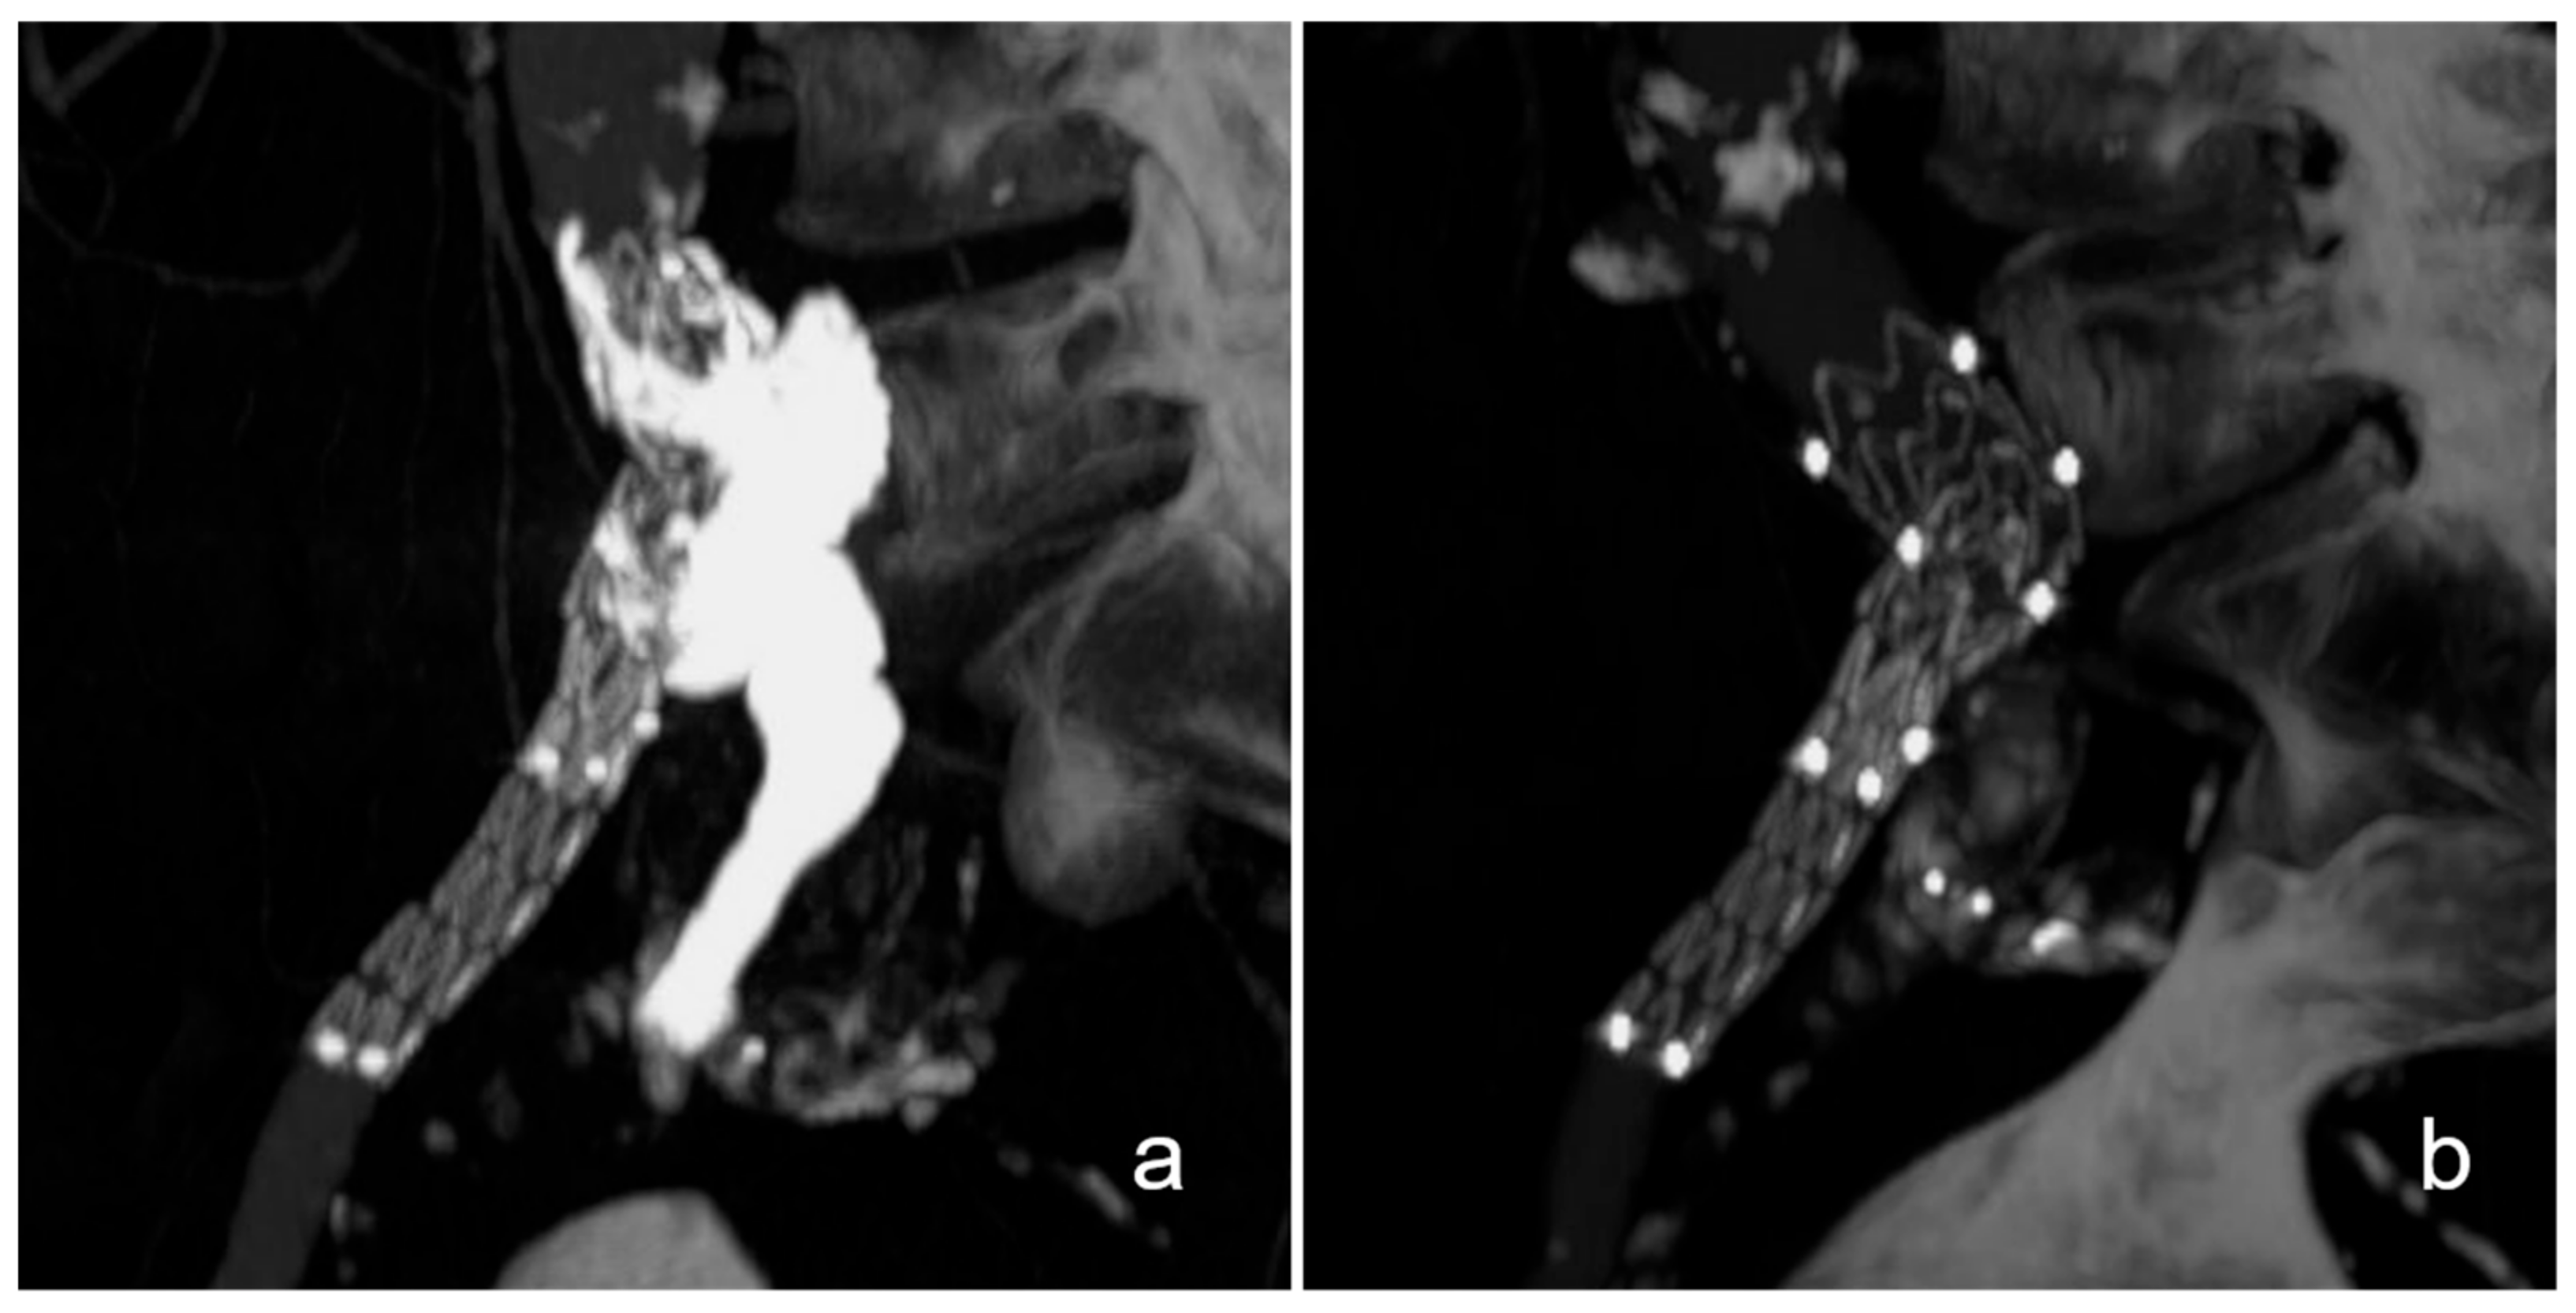

Figure 1.

Exemplary case of an aortobiiliac aneurysm with rupture of the left external iliac artery. This patient presented with an aortobiiliac aneurysm with rupture of the left external iliac artery (a). After plug embolization of the left internal iliac artery, aneurysm repair was completed with standard EVAR while jailing a 5 French catheter inside the aneurysm at the rupture site (arrow, (b)). Finally, the rupture site was embolized with N-butyl-cyanoacrylate and lipiodol, which can be seen as a ball-shaped radiopacity on the left external iliac artery (star, (c)).